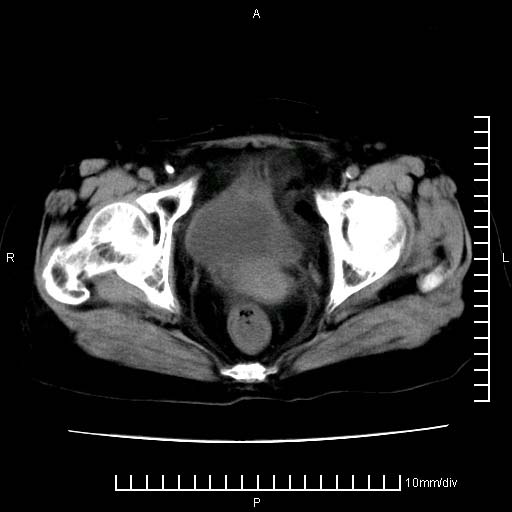

下腹疼痛2月,加重并呕吐2天,下腹压痛,反跳痛。白细胞1万2.

下腹至盆腔较大包块,与邻近肠管关系密切,下腹疼痛2月,加重并呕吐2天,下腹压痛,反跳痛。白细胞1万2.

补充:道格拉斯腔内有积液,且密度较高,显然提示有感染。

附件实性肿块有坏死 考虑卵巢癌

来源于附件占位—多考虑:卵巢癌!

有病理了,楼上的哥们你说对了

感谢楼主反馈术后病理结果(卵巢癌),学习了!